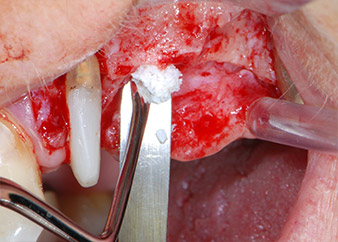

Prima di procedere al posizionamento dell'impianto, il tessuto infetto è stato rimosso dall'osso alveolare nel sito di impianto e attorno ai denti di appoggio con un attacco progettato per la sagomatura ossea e per la raccolta di frammenti ossei (Piezomed, attacco B5) (Figg. 6 e 7).

strumento piezoelettrico di raschiatura

Fig. 6: Il sito chirurgico è stato sbrigliato con uno strumento piezoelettrico di raschiatura per raccogliere frammenti ossei e modellare il tessuto osseo.

Le mancanze di tessuto osseo attorno gli impianti, in corrispondenza dell'aspetto mesiale del dente 27 e attorno alla radice buccale del dente 24, sono stati riempiti con particelle xenogeniche di sostituzione ossea e coperte con una membrana di collagene assorbibile (Bio-Gide, Geistlich Biomaterials) per tecnica di innesto GBR (Figg. 13 e 14).

Materiale xenogenico di sostituzione ossea

Fig. 13: È stato usato materiale xenogenico di sostituzione ossea per riempire i difetti ossei rimanenti...